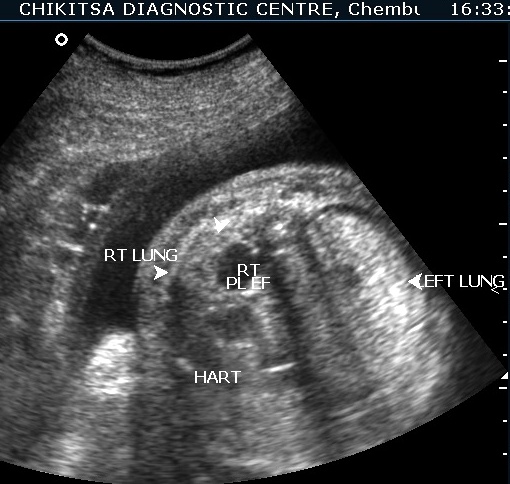

The left lung is hyperechoic and enlarged.

The heart is pushed to the right side, is compressed and therefore small.

The right lung is compressed and hypoplastic.

There is hydrops due to cardiac failure : bilateral pleural effusion, a small amount of ascites and generalised edema in the sub-cutaneous tissue.